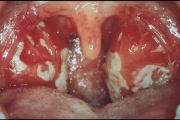

Infektsioosne mononukleoos (suudlemisnakkus), Epstein-Barri viirus (EBV)

Mononukleoos põetakse sageli läbi juba lapseeas. Väikelastel kulgeb nakkus enamasti sümptomiteta, kuid noortel ja täiskasvanutel kujuneb välja mononukleoosi haiguspilt. Peale nakatumist jääbEpstein-Barr viirus vaikselt kogu eluks organismi, elades neelus ja spetsiifilistes immuunsüsteemi Loe edasi »